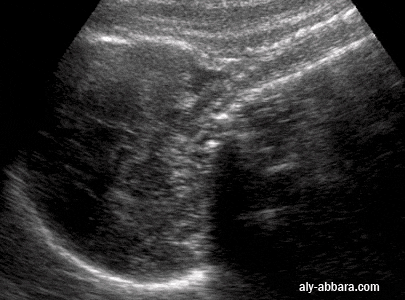

Image échographique montrant une flexion et une déflexion de la tête fœtale

Image montrant une flexion et une déflexion de la tête foetale

• La déflexion de la tête fœtale :

• La déflexion de la tête fœtale modifie l'angulation entre le rachis cervical et l'os occipital du crâne ; l'angle qui est normalement obtus devient aigu, comme l'on peut constater sur cette image échographique.